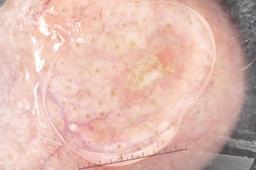

{

"age_approx": 75,

"anatom_site_general": "head/neck",

"concomitant_biopsy": true,

"dermoscopic_type": "contact non-polarized",

"diagnosis_1": "Malignant",

"diagnosis_2": "Malignant melanocytic proliferations (Melanoma)",

"diagnosis_3": "Melanoma in situ",

"diagnosis_confirm_type": "histopathology",

"image_type": "dermoscopic",

"lesion_id": "IL_7473586",

"melanocytic": true,

"sex": "female"

}